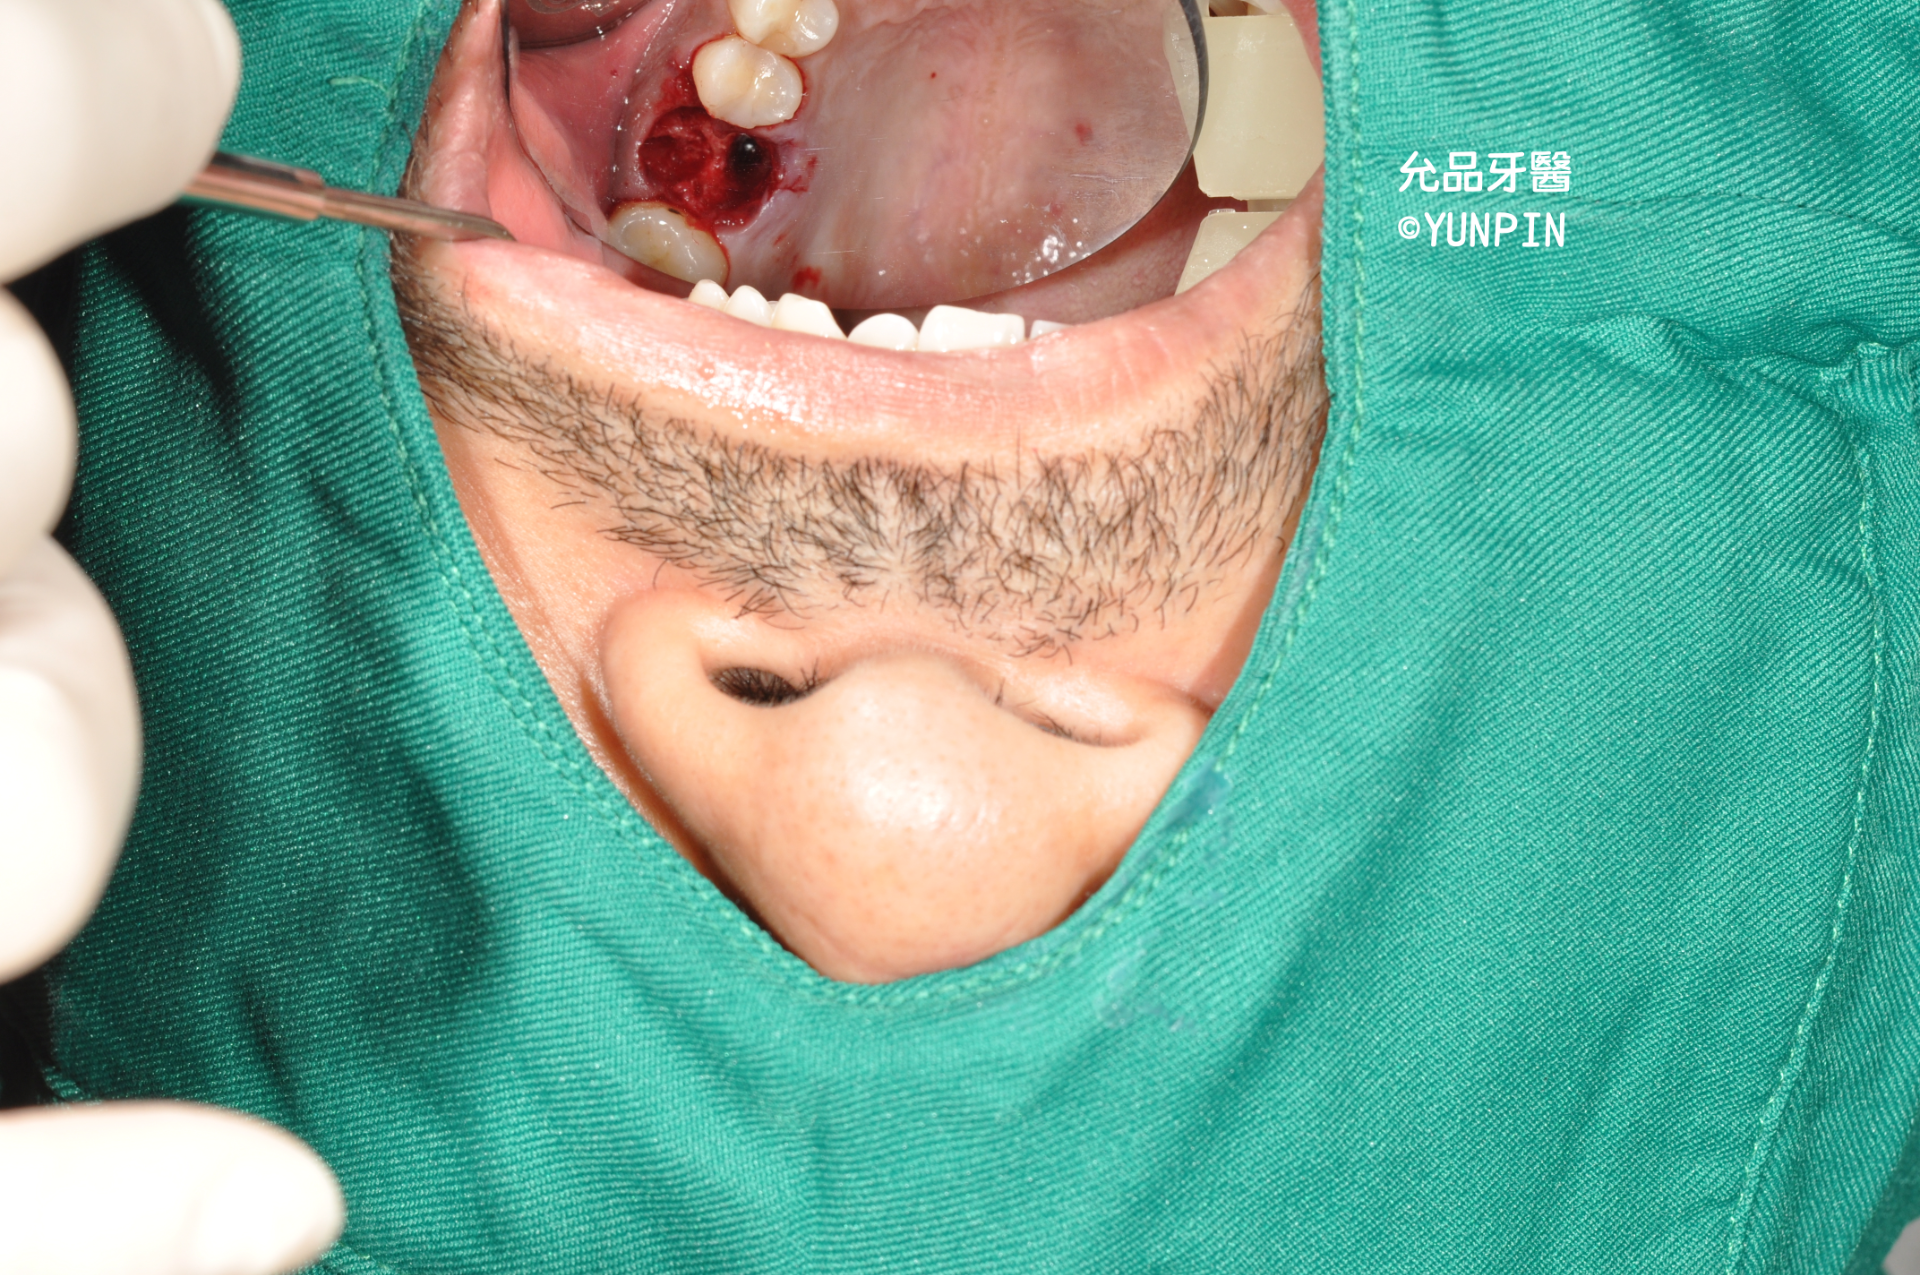

齒槽骨脊保存術socket preservation

患者主訴牙痛,他家診所檢查為牙裂,口內實際狀況已有明顯裂痕

討論完建議施作齒槽骨脊保存術,保留牙窩空間以利後續重建。